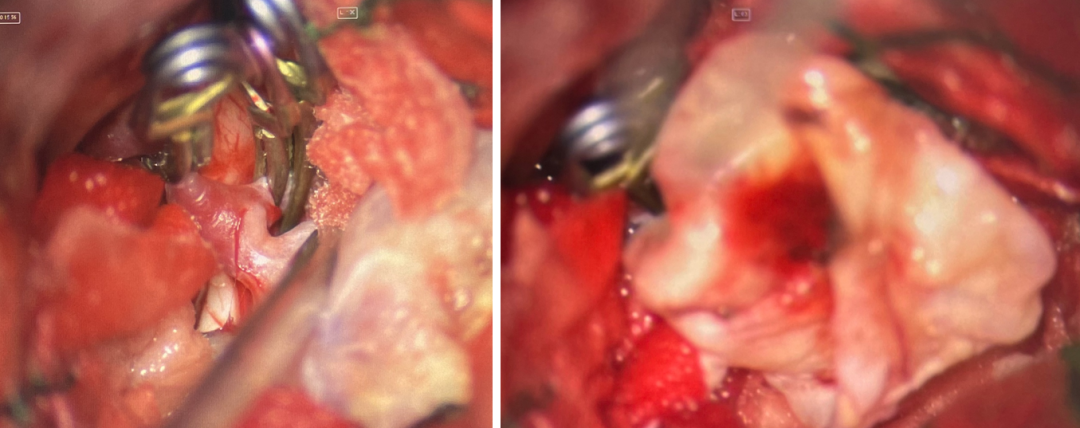

术前诊断:

术中电生理未见明显异常,因此未进行进一步血流重建处理。